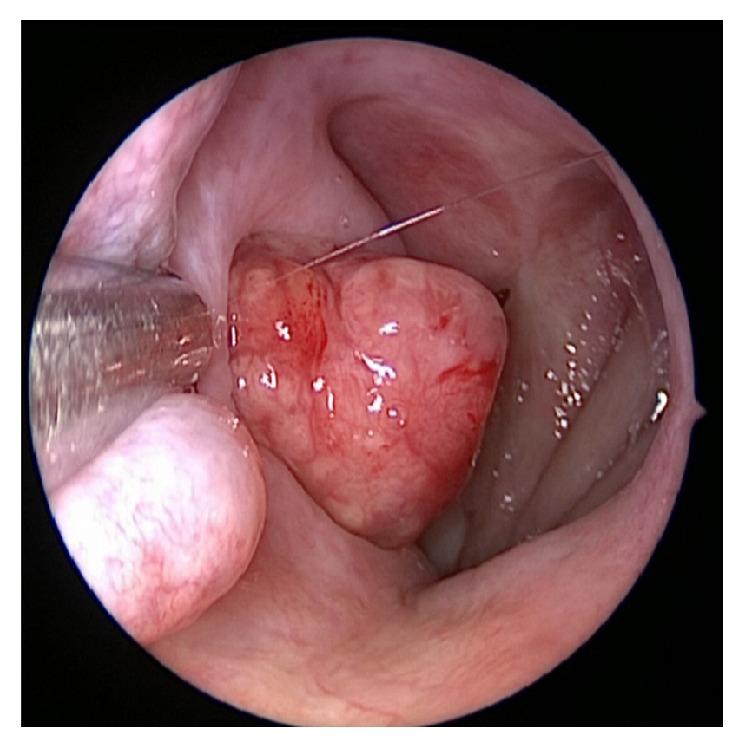

Primary sinonasal and middle ear neuroendocrine carcinomas are rare malignancies of the head and neck. Owing to the rarity of these tumors, the clinical behavior and optimal management of these tumors are not well defined. We present a case of an incidentally discovered sinonasal neuroendocrine carcinoma that was found to originate from the Eustachian tube, which has not previously been described in the literature. This patient was treated with primary surgical resection using a combination of transnasal and transaural approaches and achieved an incomplete resection. Follow-up imaging demonstrated continued tumor growth in the Eustachian tube as well as a new growth in the ipsilateral cerebellopontine angle and findings suspicious of perineural invasion. However, the tumor exhibited a benign growth pattern and despite continued growth the patient did not receive additional treatment and he remains asymptomatic 35 months following his original surgery.